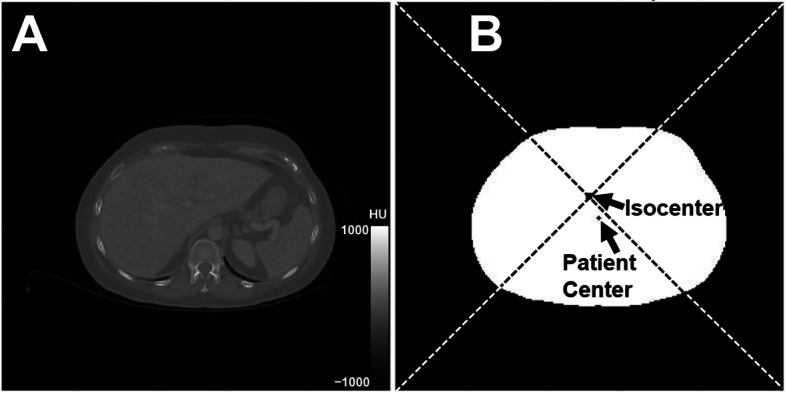

Method: The digital-BGO PET/CT with AI-based auto-positioning was compared (χ2, Mann-Whitney tests) to a solid-state lutetium-yttrium oxyorthosilicate (digital-LYSO) PET/CT with manual patient positioning (n = 432 and 343 studies each, respectively), with results split into groups before and after the date of a recalibration of the digital-BGO auto-positioning camera. To measure the transverse displacement of the patient center from the scanner isocenter (off-centering), CT slices were retrospectively selected and automatically analyzed using in-house software. Noise was measured as the coefficient of variation within the liver of absolute Hounsfield units referenced to air. Radiation exposure was recorded as dose-length product (DLP). Off-centering measurements were validated by a phantom study.

Results: The phantom validation study gave < 1.6 mm error in 15 off-centering measurements. Patient off-centering was biased 1.92 ± 1.79 cm (mean ± standard deviation) in the posterior direction which was significantly different from the 0.22 ± 1.21 cm bias in the left lateral direction (p < 0.0001, Wilcoxon). After recalibration, 27% (38/140) of the studies had off-centering results > 2.5cm for the digital-BGO, which was significantly better than the 49% (143/292, p < 0.001) before recalibration and better than for the digital-LYSO: 54% (119/222, p < 0.001) before and 55% (66/121, p < 0.001) after. On average, CT image quality was superior for non-obese patients who were most closely aligned with the isocenter: noise increased by 3.2 ± 0.1% for every 1 cm increase in off-centering. DLP increased by 144 ± 22 Gy cm for every 1 cm increase in anterior off-centering.